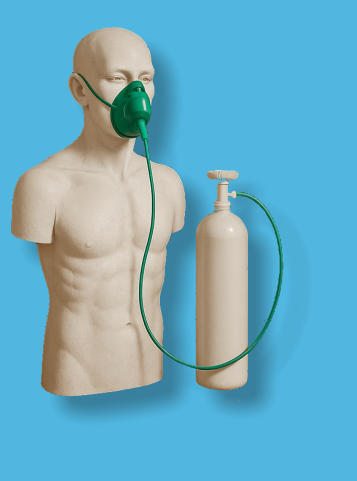

- Was bedeutet IHHT?

- Wobei kann es helfen?

- Funktionsweise

- Wie läuft eine IHHT ab?